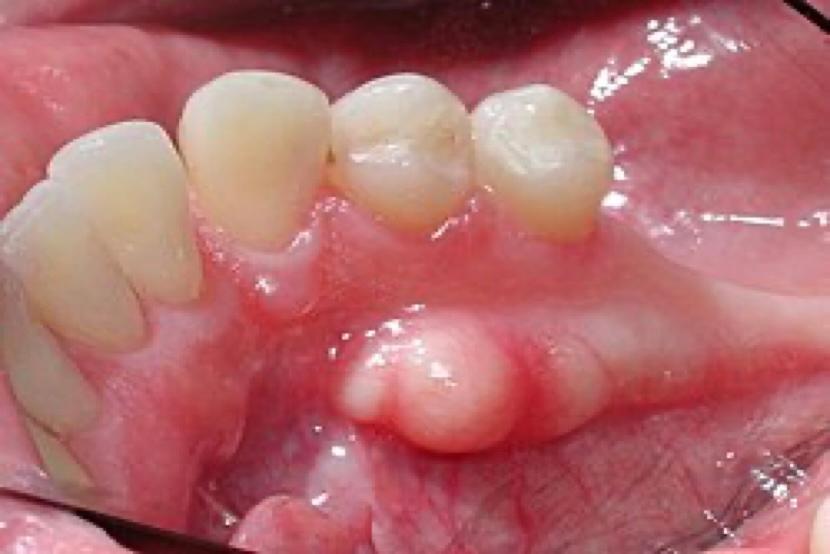

3. On the side of the lower molar teeth. Here is a picture of one of these in Dr Power’s mouth:

The good news is that all of the pictures shown above are completely normal and are no more likely to change into anything abnormal than any other part of the mouth. The bad news is that they will continue to grow over our lifetime. The larger ones can get in the way and can get scratched by sharp foods or toothbrush head, or when taking impressions in the mouth, or when wearing a denture (if a person has one).